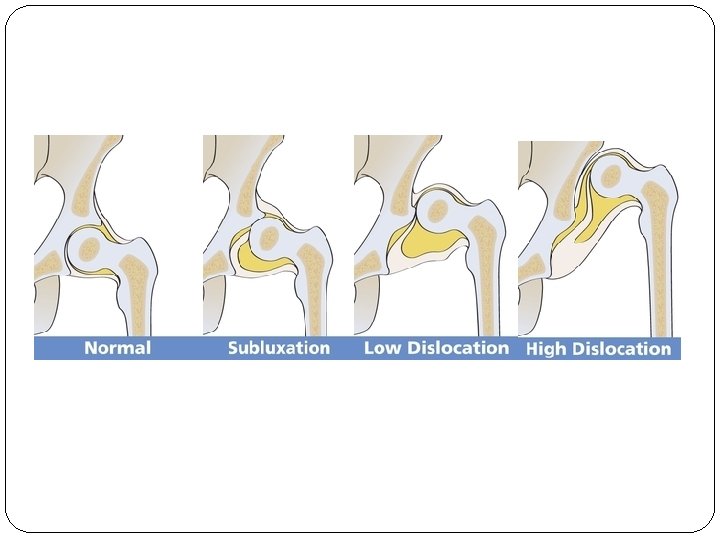

Definition of DDH: �It’s a spectrum of abnormalities affecting the growing hip. �A condition where the hip joint is not formed properly where the acetabulum is too shallow (acetabular dysplasia) and the femoral head is sublaxed or dislocated. �Whether the instability comes first and then affects acetabular development because of imperfect seating of the femoral head, or is a result of a primary acetabular dysplasia, is still uncertain.

Cont… �The old term for such condition used to be congenital dislocation of the hip (CDH) because they thoughi it occur in the first month. In the case of DDH, the infant/child’s joint is otherwise normal except for the instability, leading to abnormal growth of the hip joint. The term DDH also describes the range and evolution of abnormalities that occur in this condition. It is NOT a one step disease !!

Cont …. Pathology: a. The acetabulum is shallow (shaped like a saucer instead of a cup). b. The femoral head gets dislocated. c. The capsule is stretched and the ligamentum teres becomes elongated and hypertrophied. Two forms of femoral dysplasia are: Coxa vara, in which the femur head grows at too narrow an angle to the shaft. Coxa valga, in which the angle is too wide.

Types of DDH according to severity: Dislocated. In the most severe cases of DDH, the head of the femur is completely out of the socket. Dislocatable. In these cases, the head of the femur lies within the acetabulum, but can easily be pushed out of the socket during a physical examination. Subluxatable. In mild cases of DDH, the head of the femur is simply loose in the socket. During a physical examination, the bone can be moved within the socket, but it will not dislocate.